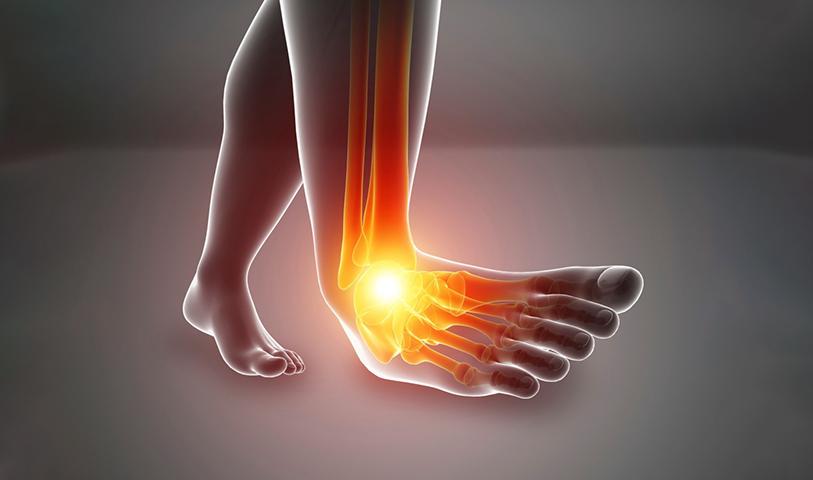

발목불안정증

발목 인대가 약해져서 올바른 역할을 하지 못하고 습관적으로 발목을 삐게 되는 질환으로,

발목 인대 손상 후 치료를 하지 않은 상태에서 빈번하게 발생 됩니다.

발목불안정증을 방치하게 될 경우 발목 염좌로 이어질 수 있으며

인대 조직까지도 손상을 입힐 수 있습니다.